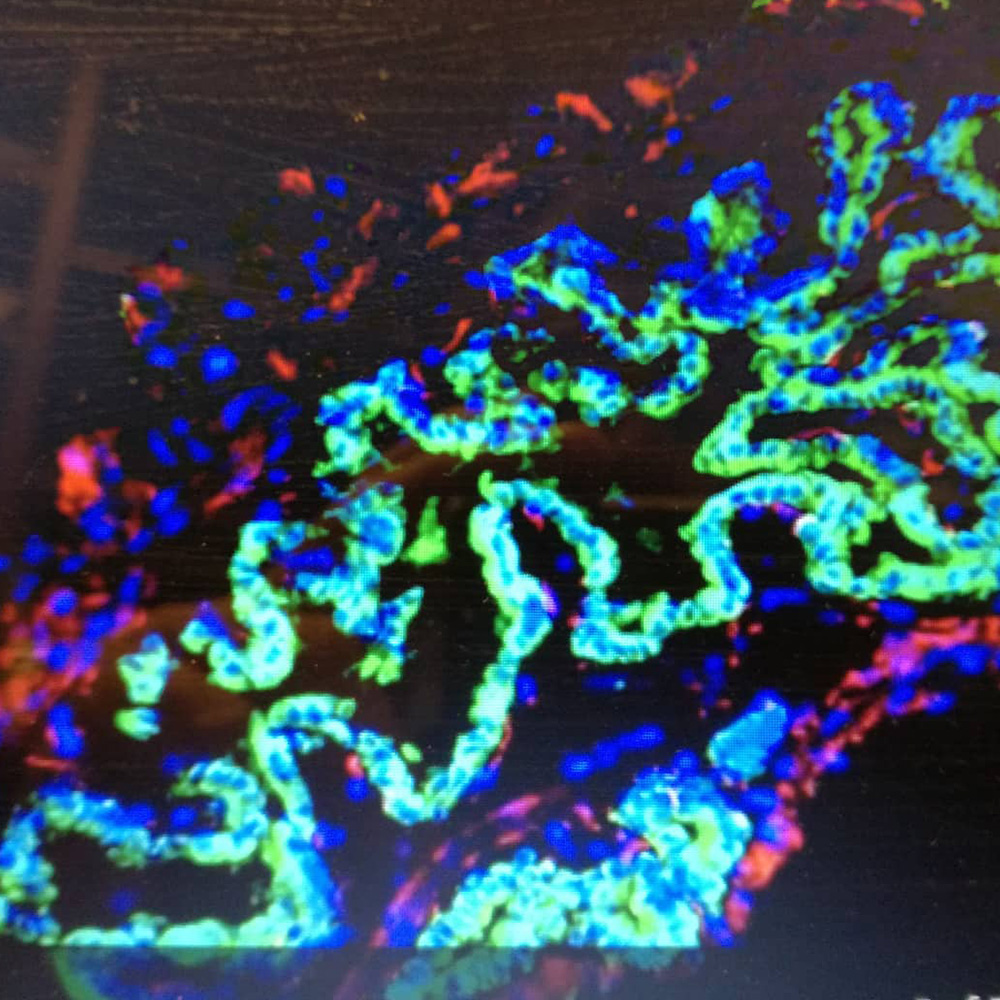

2013 yılında embriyonik kök hücreler kullanılarak, bağışıklık sisteminin en önemli organlarından biri olan insan TİMUS dokusu vücut dışında üretilmiştir. Kullandığımız kelime ve dokuları tanımalıyız, bu yavaş ilerlememize neden olsada, öğrenmemizi...

Moleküler Biyoloji ile yüksek bir ivme kazanan Biyoteknoloji ve Genetik Mühendisliği birlikte çalışarak harikalar yarattıkları bir dönemin kapısını araladılar.Kök hücrelerinden bahsederken bunların ileride çok yararlı olacakları bir...